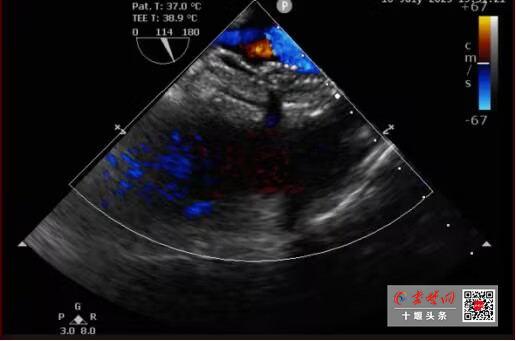

• 全国首例!十堰人医“双降解”封堵术巧补心脏双“洞”不留痕

全国首例!十堰人医“双降解”封堵术巧补心脏双“洞”不留痕

今日房县网讯 通讯员 秦洪涛  马婷婷 沈俊 报道:近日,十堰市人民医院心脏中心实现重大突破,成功为一名27岁双孔型房间隔缺损(ASD)患者植入全国首例双生物可降解封堵器。这项高难度手术的圆满成功,不仅完美修复了患者的心脏,更…